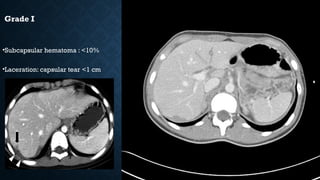

AMERICAN ASSOCIATION FOR THE

SURGERY OF TRAUMA (AAST) GRADE

I

• Subcapsular hematoma <10%

• capsular laceration <1 cm depth

Grade I

•Subcapsular hematoma : <10%

•Laceration: capsular tear <1 cm